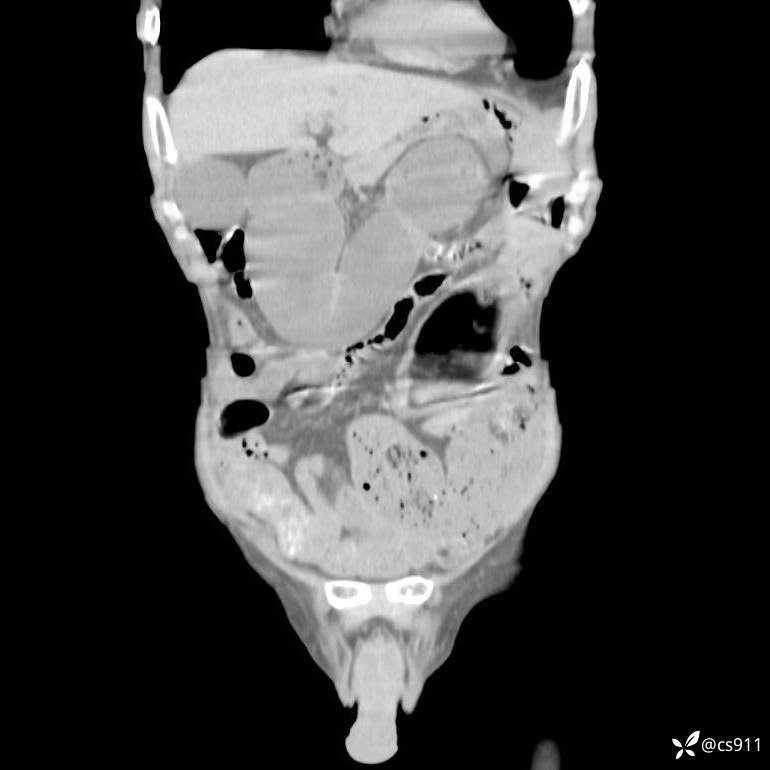

急腹症之急诊CT,原因?答案公布

男,77岁,腹痛、腹胀伴恶心呕吐1天。呕吐胃内容物,非喷射性呕吐,有咖啡色样胃内容物,诉有胃穿孔病史。查体:全腹平,下腹部压痛,全腹无反跳痛,叩诊呈浊音,移动性浊音阴性,肠鸣音减弱,1-2次/分。肛检:直肠未扪及明显肿物,可触及大量粪块。

T 36.6℃ P 80次/分 R 26次/分 BP 100/60mmHg

白细胞(WBC) H 14.55 10e9/L 4-10

中性粒细胞百分率(NEUT%) H 85.7 % 40-75

血淀粉酶(AMY) HH 1859 U/L 35-135

癌胚抗原(CEA) H 27.44 ng/ml 0-5

呕吐物 潜血试验 * 阳性 阴性

患者轮椅入室检查神志清楚, 能配合摆位和呼吸